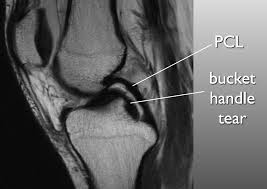

Meniscal tear can be well appreciated on an mri. In humans they are present in the knee, wrist, acromioclavicular, sternoclavicular, and temporomandibular joints; In other animals they may be present in other joints.

Circle of villis angiogram anatomy mri. The posterior horn is always larger than the anterior horn. Meniscus rupture can occur with a sharp movement in the lateral direction, or in a direction that goes beyond the. Magnetic resonance (mr) imaging of the knee and ankle is playing an increasingly important role in the detection, diagnosis and prognosis of these injuries and their associated complications.